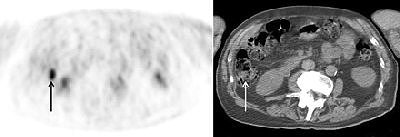

![]() |

| Focal colonic FDG standardized uptake value (SUVmax = 7) was shown in cecum, with fecal stasis (arrows) on CT image. Colonoscopy was negative (patient 8). Gutman F, Alberini J-L, Wartski M, Vilain D, Le Stanc E, 3, Sarandi F, Corone1 C, Tainturier C, Pecking AP. "Incidental Colonic Focal Lesions Detected by FDG PET/CT" (AJR 2005; 185:495-500). |